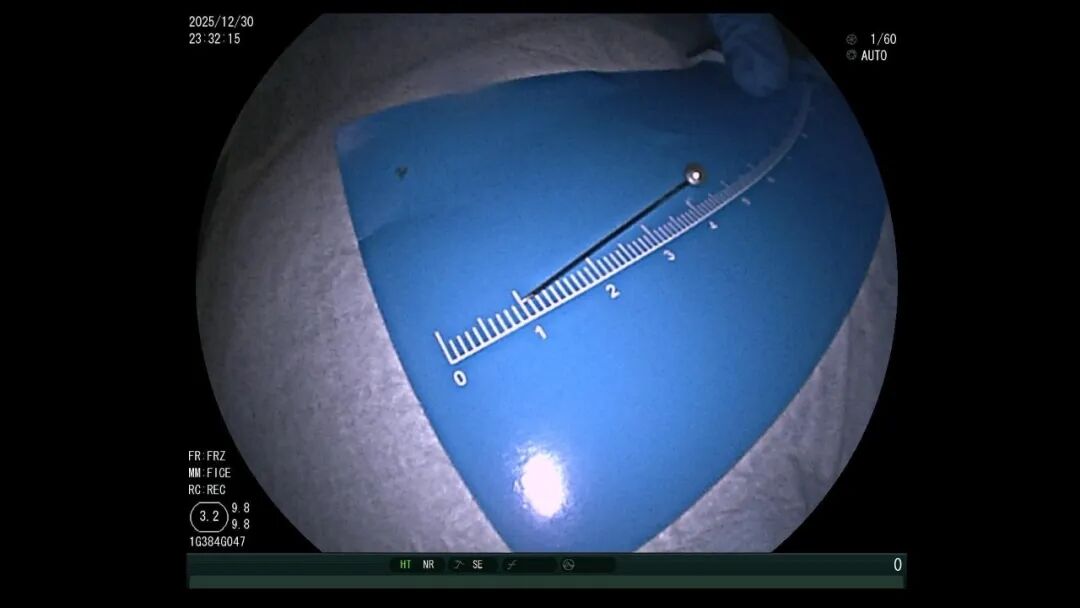

异物难寻:3.5厘米的大头针混在食物残渣中,定位难度极高

起初,医生尝试用异物钳和网兜抓取均告失败。随后调整方案,改用圈套器配合透明帽,小心将大头针调整为竖直状态,避免取出时横向划伤食管

医生一边引导孩子配合,一边精准操控器械,最终成功取出大头针,未造成黏膜损伤